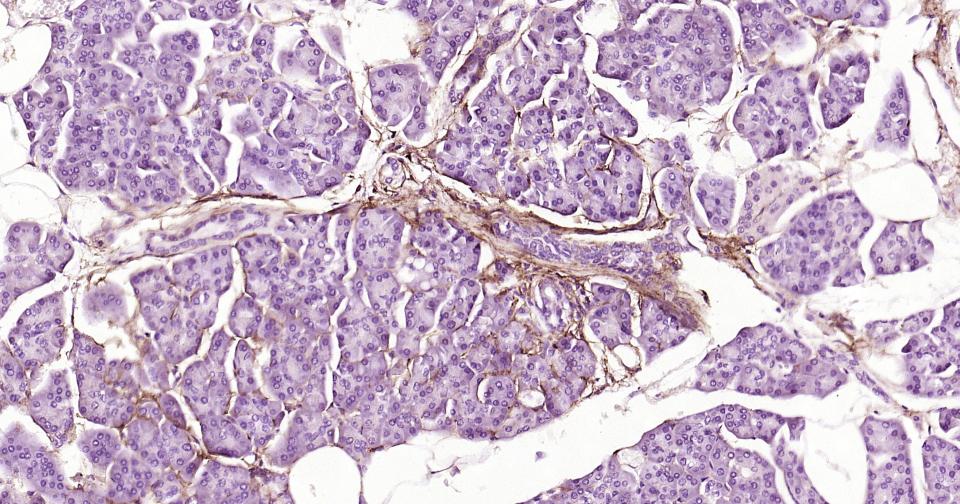

IHC-PHuman, Mouse, Rat1:100-500

交叉反应: Human, Mouse, Rat